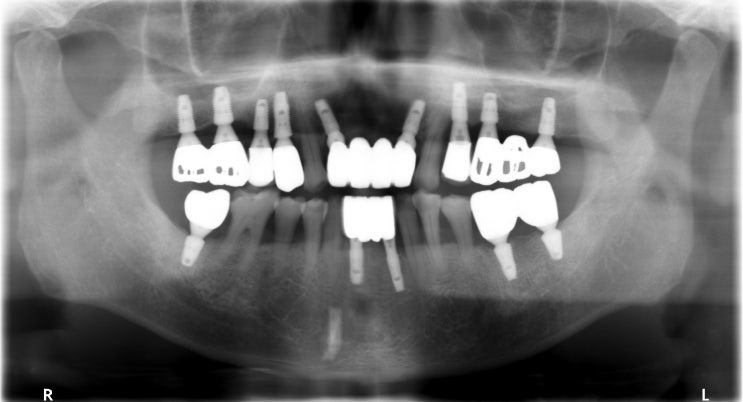

[조훈치과] 치아 상실 후 임플란트 식립 치료 증례

안녕하세요. 조훈 치과입니다. 치아 상실의 원인은 여러 가지가 있습니다. 충치 및 치주 질환이 악화된 경...